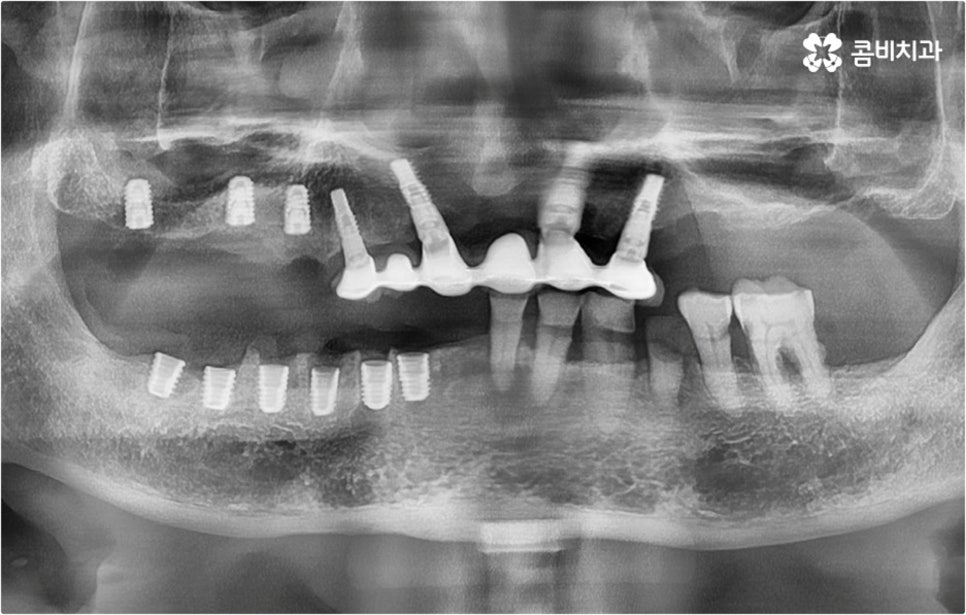

예를 들어 사고를 통해 한꺼번에 여러 개의 치아가 부러지거나 빠진 경우 연령 또는 전신 질환 여부 등을 살펴보고 치조골 상태가 양호하다면 보다 빠르고 간편한 당일 식립 방식을 이용해 볼 수 있어요. 그러나 하나 둘씩 치아가 빠질 때 마다 제때 치료를 해 주지 않아 치료 시기를 놓치고 결과적으로 무치악 상태에 이른지 오래 된 경우 또는 틀니를 오래 착용하여 잇몸뼈가 이미 많이 내려앉은 경우라면 바탕이 되는 잇몸뼈를 보충해 준 후 식립을 진행하는 방식을 이용해야 할 거예요.

또한 상악동과의 거리가 짧다면 거상술을 선행해야 할 수도 있고 심각한 치주 질환이 원인이라면 이를 먼저 깨끗하게 치료해 준 후 식립을 진행해야 성공률 또는 지속률이 높아질 수 있어요.

아무 것도 없는 상태에서 제대로 저작 기능을 발휘할 수 있도록 다시 구강 내부를 재현하는 전악임플란트 는 굉장히 고난도에 속하는 치료이기 때문에 충분한 임상 경험을 가지고 있는 숙련된 의료진과 함께 하실 필요가 있어요. 전악임플란트 방식이 빠진 영구치 자리마다 다 임플란트를 식립하는 것이 아니라, 상하악 각각에 8~12개 정도로 필요한 최소한의 인공 치근을 심고 그 사이 사이는 브릿지 방식으로 보철물을 연결하는 것이기 때문에 저작력을 골고루 분담하여 안정적인 지속성을 높일 수 있도록 환자 개개인의 상태에 맞게 인공 치근의 위치, 각도, 간격, 심는 깊이 등을 세밀하게 설정하여 교합을 제대로 맞출 수 있는 시술자의 뛰어난 기술력과 풍부한 노하우가 요구되는 거예요.

또한 이를 위해서 치아 주변 조직과의 거리나 잇몸뼈 높이, 밀도 등을 정확하게 파악할 수 있도록 도와주는 3D CT와 같은 정밀 진단 장비를 갖추고 환자분들의 상황에 맞는 계획을 세워 무리하지 않게 진행할 수 있는 체계적인 시스템을 운용하는 치과에서 임플란트 시술을 받으실 필요가 있어요. 만약 치과내 자체 기공소를 갖추고 있다면 보철물 제작에 대한 피드백이 보다 빠르게 전달, 반영될 수 있어 환자분들이 이용하시기에 좀 더 편안하실 거예요.